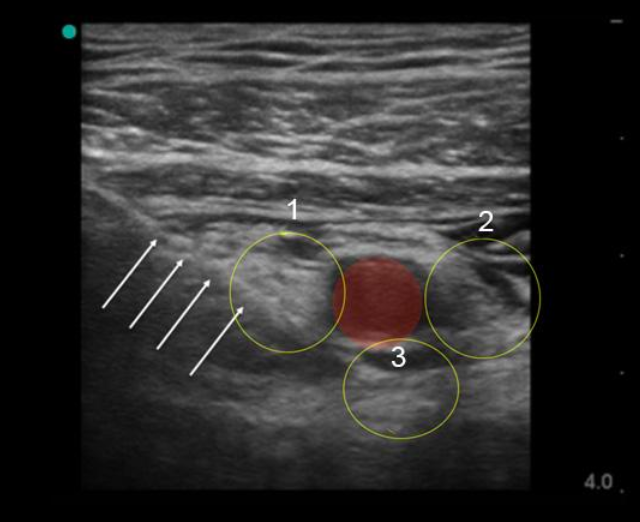

Infraclavicular Ultrasound Technique 1 Image